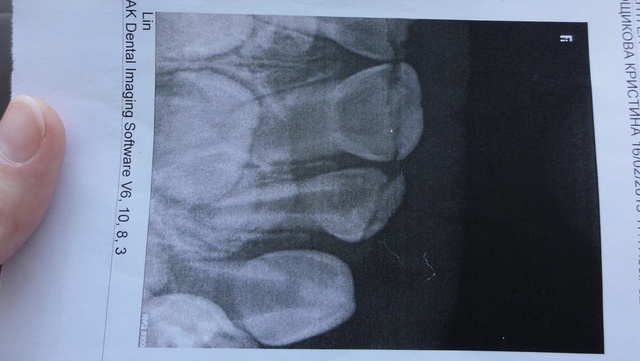

Ребенок плачет,т.к. передние зубы сломаны (

На это указывает поперечная полоса на снимке.

Зубы удалять не нужно! Их можно вылечить, удалив нерв и запломбировав каналы. И они прослужат еще долгое время!